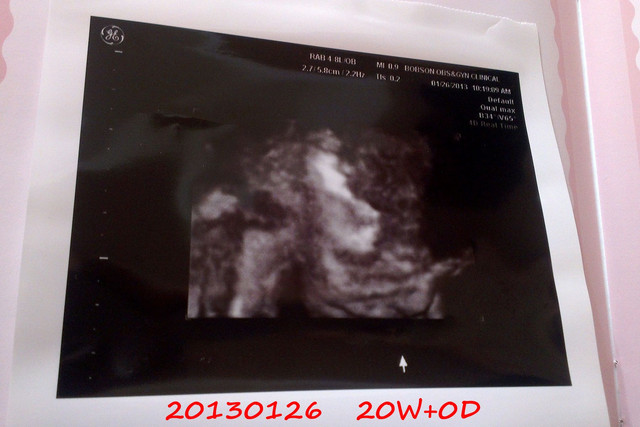

看看一開始產檢醫生幫我拍的照片

章魚妹妹在打呵欠啊

嘴巴張這麼大

還是最後笑起來的比較可愛

章魚妹

頭圍:

8.58 cm

肚圍:

32.44 cm

加起來重量為

2826g